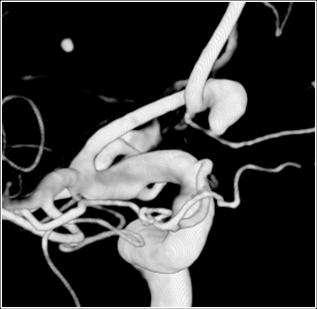

Endovascular occlusion of aneurysms includes the use of detachable coils. This is a angiographic procedure where a small soft catheter is introduced into the blood vessel from the leg artery. From there the catheter is carefully threaded up into the brain and the tip of the catheter is placed in the aneurysm (figure 6). Then through the catheter small soft coils are introduced into the aneurysm to block it completely (figure 7).

Figure 6. The catheter is carefully threaded up into the brain.

Figure 7. Endovascular occlusion of aneurysms includes the use of detachable coils.

This technique of treating aneurysms with coils was invented at UCLA in 1990 and the first patient in the world was treated here in 1991. Since then, more than 1300 patients have been treated with this technique at UCLA.